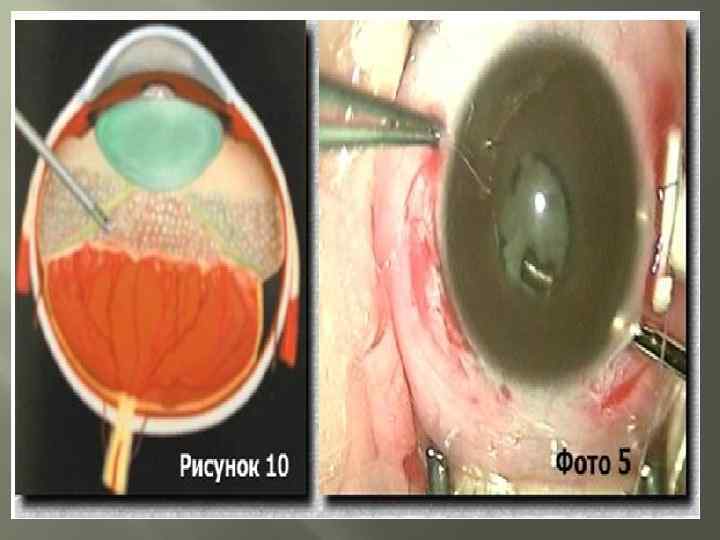

Лечение Хирургическое лечение - применяют при быстропрогрессирущих, далекозашедших стадиях(4 -5 стадия и «плюс» -болезнь) Склеропломбирование- установка с внешней стороны глаза «заплатки» которая придавливает стенки глаза к отслоившейся сетчатке. Эффективна при небольших отслойках. Благоприятным исходом можно считать улучшение зрения либо остановку ухудшения зрения Витректомия - удаление стекловидного тела. Применяется при больших отслойках сетчатки и массивных кровоизлияниях в стекловидное тело, а так же при неэффективности пломбирования склеры. Т. к. выполняется при серьезных изменениях сетчатой оболочки прогноз не всегда благоприятный.

Лечение Хирургическое лечение - применяют при быстропрогрессирущих, далекозашедших стадиях(4 -5 стадия и «плюс» -болезнь) Склеропломбирование- установка с внешней стороны глаза «заплатки» которая придавливает стенки глаза к отслоившейся сетчатке. Эффективна при небольших отслойках. Благоприятным исходом можно считать улучшение зрения либо остановку ухудшения зрения Витректомия - удаление стекловидного тела. Применяется при больших отслойках сетчатки и массивных кровоизлияниях в стекловидное тело, а так же при неэффективности пломбирования склеры. Т. к. выполняется при серьезных изменениях сетчатой оболочки прогноз не всегда благоприятный.